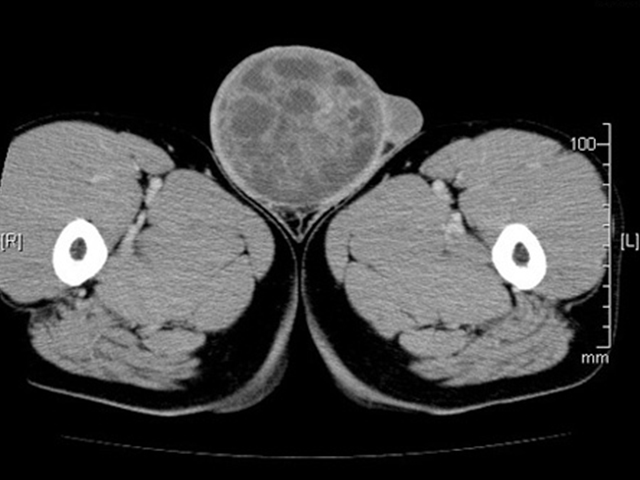

精巣がんのリスクがあるのは誰ですか?

家族歴は精巣がんのリスクを大幅に高める可能性がありますが、他の危険因子も関与しています。これらには次のものが含まれます。

停留精巣

停留精巣(停留精巣)があると、次のような理由で精巣のリスクが高まる可能性があります。

精巣がんが発症すると、

これは、停留精巣が精巣がんの原因ではないことを示唆しています。むしろ、別の健康状態が精巣がんや停留精巣のリスクを高める可能性があります。